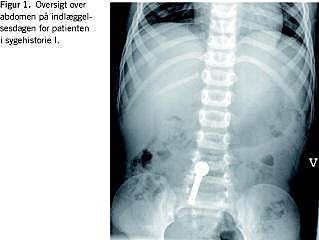

I. En fireårig dreng blev indlagt, efter at han dagen forinden havde slugt to Geomag-magneter (kugle og stav). Patienten havde efter indtagelsen klaget over intermitterende mave-smerter, men havde ingen yderligere symptomer. Ved modtagelsen var han alment upåvirket. Abdomen var blødt og uømt med naturlige tarmlyde. En oversigt over abdomen viste, at de to magneter var passeret til tyndtarmen, og at de sad sammen (Figur 1 ). Patienten blev observeret tæt og blev udskrevet i sin habituelle tilstand dagen efter.